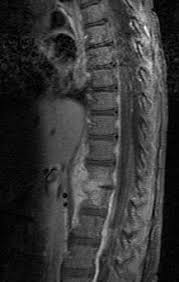

Spondylosis deformans, deutsch spondylose (auch wirbelsäulenverschleiß genannt), ist ein sammelbegriff für degenerative veränderungen an wirbelkörpern (und intervertebralräumen), die sich röntgenologisch als unregelmäßigkeiten (z.

Man nutzt sie beispielsweise zur diagnostik von knochenbrüchen, aber auch von krankheiten des brustraums (wie lungenentzündung, vergrößerung des herzmuskels bei herzschwäche, aussackungen der aorta) oder bauchraums (wie darmverschluss, gallensteine). Zacken, erhebungen oder randwülste) darstellen. Atelektazi, akciğerin bir kısmının ya da akciğerlerden birinin tamamen büzüşmesi sonucu yeterince genişleyememesi ve böylece işlevini yitirmesidir.atelektazi durumunda daha az hava içeren akciğer parankimi oluşur. Spondylosis deformans, deutsch spondylose (auch wirbelsäulenverschleiß genannt), ist ein sammelbegriff für degenerative veränderungen an wirbelkörpern (und intervertebralräumen), die sich röntgenologisch als unregelmäßigkeiten (z. Aug 21, 2018 · röntgen des knochensystems zur diagnose von knochenbrüchen, verschleiß, entzündungen und verletzung von gelenken, sehnen oder bändern röntgenuntersuchungen des kopfes zur feststellung von schädelbrüchen und entzündungen der nasennebenhöhlen. Darunter versteht man die einfachste art einer röntgenuntersuchung. We would like to show you a description here but the site won't allow us. In its primary application of medical imaging, a fluoroscope (/ ˈ f l ʊər ə s k oʊ p /) allows a physician to see the internal structure and function of a patient, so that the pumping action of the heart or the motion of swallowing, for. Die untersuchung kann bei der diagnose einer vielzahl von erkrankungen helfen und kommt dementsprechend oft zum einsatz.